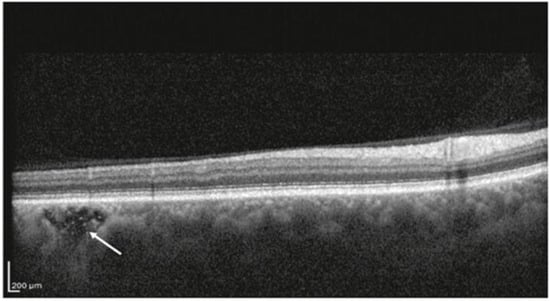

- Sura, A.A.; Chen, L.; Messinger, J.D.; Swain, T.A.; McGwin, G., Jr.; Freund, K.B.; Curcio, C.A. Measuring the Contributions of Basal Laminar Deposit and Bruch’s Membrane in Age-Related Macular Degeneration. Investig. Ophthalmol. Vis. Sci. 2020, 61, 19. [Google Scholar] [CrossRef] [PubMed]

- Sarks, S.; Cherepanoff, S.; Killingsworth, M.; Sarks, J. Relationship of Basal laminar deposit and membranous debris to the clinical presentation of early age-related macular degeneration. Investig. Ophthalmol. Vis. Sci. 2007, 48, 968–977. [Google Scholar] [CrossRef] [PubMed]

- Won, J.; Takahashi, H.; Ploner, S.B.; Karbole, W.; Abu-Qamar, O.; Yaghy, A.; Marmalidou, A.; Kaiser, S.; Hwang, Y.; Lin, J.; et al. Topographic Measurement of the Subretinal Pigment Epithelium Space in Normal Aging and Age-Related Macular Degeneration Using High-Resolution OCT. Investig. Ophthalmol. Vis. Sci. 2024, 65, 18. [Google Scholar] [CrossRef]

- Fragiotta, S.; Parravano, M.; Sacconi, R.; Costanzo, E.; Viggiano, P.; Prascina, F.; Capuano, V.; Souied, E.H.; Querques, G. A Common Finding in Foveal-Sparing Extensive Macular Atrophy with Pseudodrusen Implicates Basal Laminar Deposits. Retina 2022, 42, 1319–1329. [Google Scholar] [CrossRef]